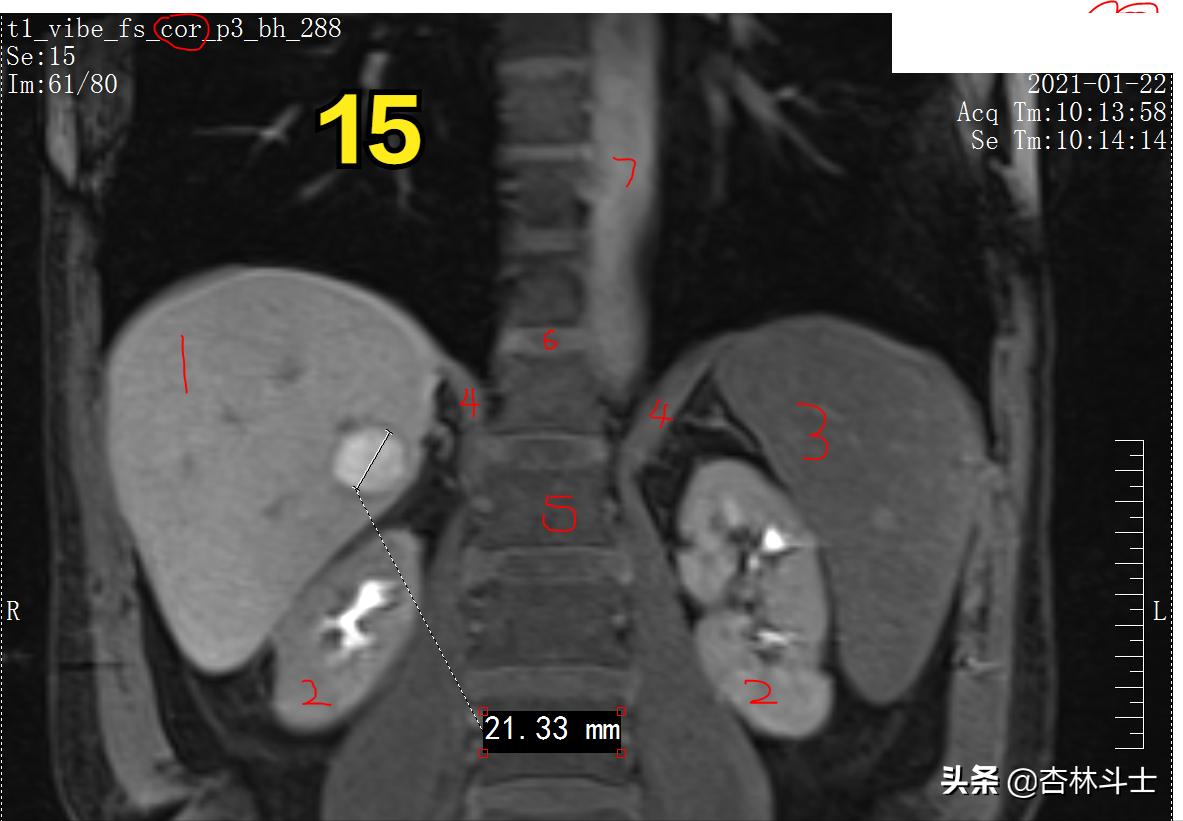

图15 T1加权压脂肝胆特异期冠状位

图15中 1、肝脏 2、双肾 3、增大的脾脏 4、双侧膈肌 5、椎体 6、椎间盘 7、胸主动脉